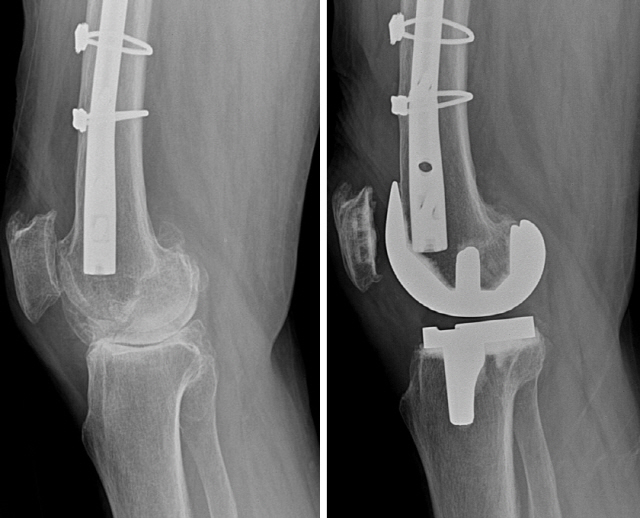

무릎주위 골절로 철심을 고정한 관절염 환자는 단순 퇴행성관절염 환자보다 인공관절수술후의 감염률이 3.5배 이상 높다.

무릎주위 골절로 철심을 고정한 관절염 환자(823명)가 단순 퇴행성관절염 환자(1640명)보다 인공관절수술후의 감염률 (4.74% 대 1.34%), 수술 및 수술 후 골절률(1.58% 대 0.55%), 재수술률 (5.47% 대 2.47%) 모두 높은 것으로 보고되었다.

따라서 외상성관절염 환자의 인공관절수술은 더욱 신중해야 한다.

서울부민병원 궁윤배 로봇수술센터장은 "컴퓨터기술의 보조(로봇, 네비게이션, 3D슌翅紈梔該瘦?로 무릎 주위에 금속고정물이 있는 환자도 안전하게 인공관절 치환술을 받을 수 있게 되었다"며 "CT기반의 사전정보 분석이 로봇인공관절수술의 적용 범위와 수술 성공에 큰 역할을 하고 있다"고 전했다.